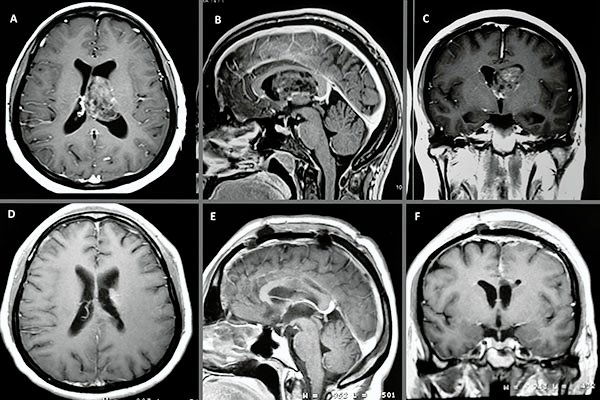

En el estudio de resonancia magnética del encéfalo se observó lesión redondeada, intraventricular a nivel de ventrículo lateral izquierdo, de bordes netos, de aproximadamente 40x30x30 mm, de señal heterogénea, predominantemente isointensa respecto a sustancia gris en T1 con presencia de focos de baja señal en su interior. En T2 se observa lesión predominantemente hiperintensa, múltiples imágenes de aspecto quístico en su interior (aspecto de burbujas) que en el FLAIR dichas imágenes quísticas son atenuadas. Tras la administración de contraste endovenoso se observa moderada y heterogénea captación del mismo (fig. 1).

Figura 1:

A, B y C) Cortes axiales en las secuencias ponderadas en T1, T2 y FLAIR respectivamente. D) Corte sagital de secuencia ponderada en T1 con contraste. E) Corte coronal de secuencia ponderada en T1 con contraste.

En la RM de encéfalo control, realizada 20 días luego de la cirugía, se observa huella de callosotomía anterior sin lesión focal intraventricular residual aparente (fig. 4).

Figura 4:

A, B y C) Cortes axial, sagital y coronal pre quirúrgicos ponderados en T1 con contraste. D, E y F) Cortes axial, sagital y coronal post quirúrgicos ponderados en T1 con contraste.